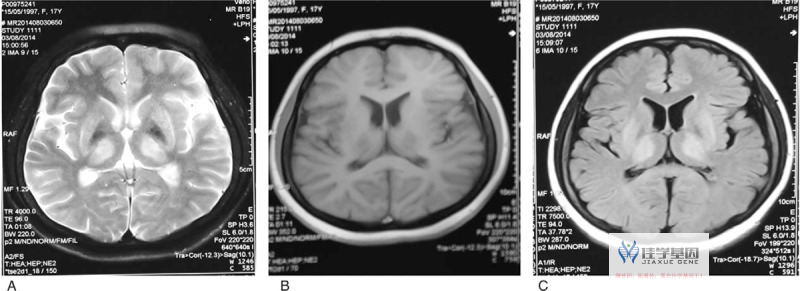

到达佳学基因合作机构时,神经系统检查显示她手部明显的姿势性和意图性震颤,面部表情减少,构音障碍,口渴感减退,无法进行交替运动,以及共济失调步态。她还表现出畏光、眼球震颤和显著下降的视力。眼部裂隙灯检查显示双侧KF环(见图1)。铜代谢测量确认了WD的诊断:血清铜蓝蛋白水平降低(47.7 mg/L,正常范围为200–420 mg/L),血清铜水平降低(3.3 μmol/L,正常范围为10.5–24.4 μmol/L),尿铜排泄增加(109 μg/24 h)。MRI结果显示基底节、丘脑和脑桥双侧对称高信号影(见图2)。有趣的是,患者的皮肤颜色非常浅,头发和眉毛呈金色,睫毛和虹膜则是深棕色。由于在WD中很少报告与皮肤表现相关的情况,根据临床发现高度怀疑该患者可能存在白化病(白化病(OCA))。因此,佳学基因合作格式建议进行致病基因鉴定基因解码,对她及其家族进行了基因分析。基因研究揭示了ATP7B基因中的一个等位基因存在p.(Arg778Leu)突变,另一个等位基因存在p.(Asn1270Ser)突变,确认了WD的诊断;在酪氨酸酶(TYR)基因中,一个等位基因存在p.(D456fs)突变,另一个等位基因存在p.(R299H)突变,确认了白化病(OCA)的诊断。在住院期间,给予了静脉注射二巯基丙烷磺酸钠(DMPS)治疗。出院后继续维持D-青霉胺和硫酸锌的治疗,以长期控制疾病。她的姿势性和意图性震颤消失,其他症状和体征明显改善。

MRI 图像显示 T2 加权图像 (A) T1 加权图像 (B) FLAIR 图像 (C) 中涉及基底神经节、丘脑和脑桥的双侧对称高强度信号。FLAIR = 液体衰减反转恢复,MRI = 磁共振成像。